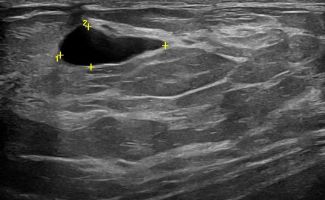

Modern ultrasound machines, equipped with advanced high-frequency transducers, techniques such as Color Doppler, Power Doppler, B-Flow, and Elastography, allow the analysis of breast architecture with exceptional accuracy.

Elastography can highlight the elasticity of a lesion, indicating whether it is hard or soft. Through this technique, we can assess the nature of the lesion, providing indications of whether it is benign or malignant. Additionally, with the contribution of Color Power Doppler and B-Flow, we can monitor the vascular flow within the lesions, offering even more information about the type and nature of the abnormality.